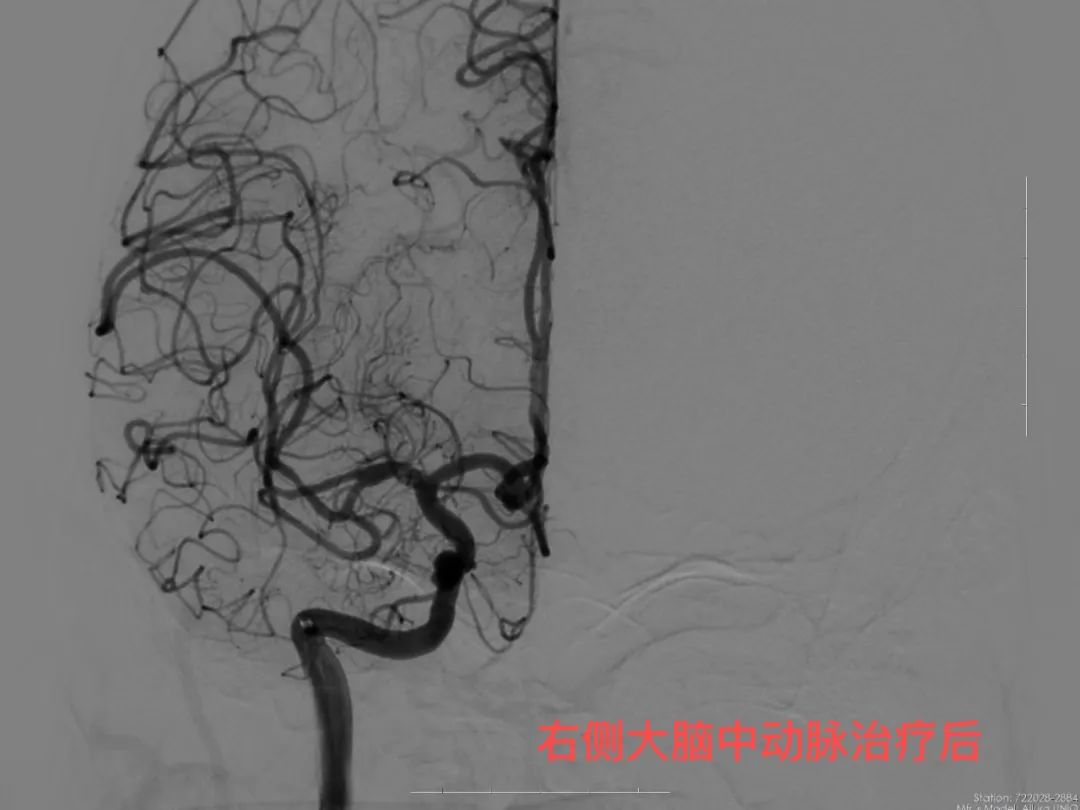

针对患者病情,神经内科团队决定行脑血管造影进一步查看。在征得患者及家属同意、排除手术禁忌症、病情稳定后即开始脑血管造影。术中发现右侧大脑中动脉M1段重度狭窄,告知患者及家属大动脉狭窄的危险性,患者及家属同意后全麻行右侧大脑中动脉球囊扩张成形术,手术顺利,患者生命体征平稳,术后患者穿刺口恢复良好,告知患者术后相关注意事项,观察两天后现患者已病情稳定出院。此次治疗,患者血管开通良好,是我院神经内科团队的又一次进步,成功减少了脑梗死复发几率,为患者后续生活质量提供了保障。